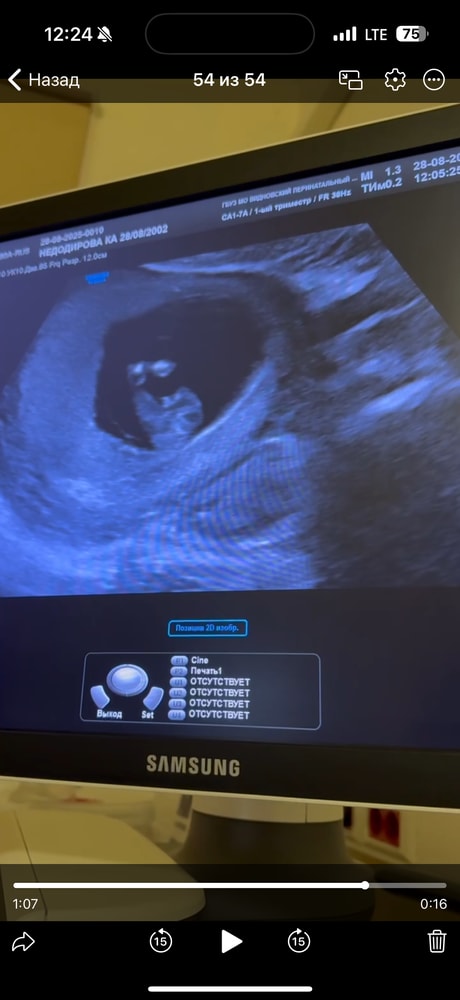

СкринингДевочки всем привет!! Сегодня была на скрининге срок 12.6

показали , что между ножек, но не сказали кто)))как думаете кто это?)))

На этом сроке смотрят с другого ракурса.

Половой бугорок в 12 недель есть у всех, смысла между ножек смотреть нет

Согласна с комментарием ниже: на этом сроке пол если и можно увидеть, то с другого ракурса, сбоку. По углу наклона.

Gaechka, да, в этом ракурсе. Там так: если угол (от спинки, позвоночника) больше 30 градусов, то мальчик, если меньше, то девочка. Вот как на фотке.

Но это ж ещё чтоб малыш лег прям поровнее на спинку.

Вроде похож больше на мальчика тут у вас, мне кажется; но, видимо, двигался на узи, попку приподнял(а). ))